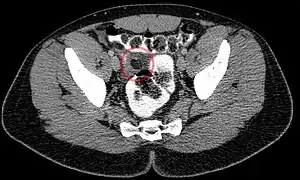

Abdominal CT scan, epiploic appendagitis (circle) -

Ultrasound and CT scans are the normal means of positive diagnosis of epiploic appendagitis. Ultrasound scans show "an oval, non-compressible hyperechoic mass with a subtle hypoechoic rim directly under the site of maximum tenderness".[5] Normally, epiploic appendages cannot be seen on CT scan.[5] After cross-sectional imaging and the increased use of abdominal CT for evaluating lower abdominal pain, EA is increasingly diagnosed. Pathognomonic CT scan data represent EA as 2–4 cm, oval shaped, fat density lesions, surrounded by inflammation. Contrasting with diverticulitis findings, the colonic wall is mostly unchanged.